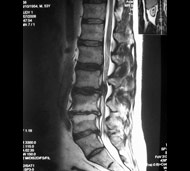

Магнітно-резонансна томографія (МРТ). У багатьох випадках саме цей тест проводять для постановки діагнозу стенозу спинномозкового каналу. У МРТ для створення зображення поперечного перерізу спини використовуються не рентгенівські промені, а потужні магнітні хвилі. Цей тест може виявити пошкодження дисків і зв'язок, а також наявність пухлин.

Комп'ютерна томографія (КТ). У цьому тесті для отримання докладного зображення певного поперечного шару (зрізу) людського тіла, включаючи форму і розмір спинномозкового каналу, використовуються рентгенівські промені.